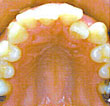

Lingual braces are attached to the inside or lingual side of the teeth to allow tooth movements to be carried out while making them completely non-visible. This advanced method makes lingual orthodontics particularly well-suited for adults and especially appealing for adults whose professions keep them in the public eyes. No one can tell they are wearing these braces. Patients can enjoy the process of orthodontia while still retaining a natural smile.

Lingual braces are hidden braces placed on the internal side of teeth. It is an invisible orthodontic treatment option that was once commonly opted as a braces for adults. Specialized orthodontist training and dental lab is required for lingual braces. Therefore, there are very few orthodontists in Thailand and around the world with the qualifications for lingual braces. At BIDC, even within our pool of orthodontists, there are only a select few specialists treating the lingual orthodontic technique and you will require an advance appointment booking if opting for lingual braces.